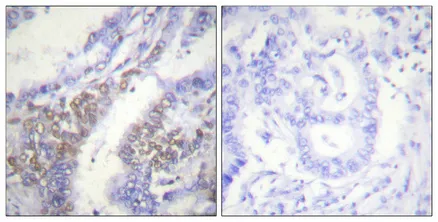

FAK (phospho Tyr397) Rabbit Polyclonal Antibody

Cat: APRab04658